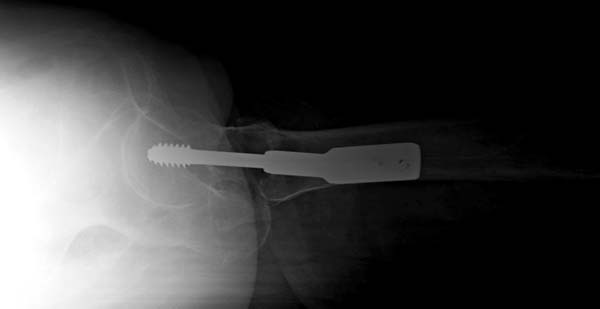

Сегодня оперировал, остеосинтез 130-град. Г-образной пластиной, из-за наступившийся трешины б/вертела дополнительно спонгиозным винтом, вроде неплохо получилось. Проблема с фотоаппаратом, как получится отправлю снимки.

Всем огромное спасибо! К стати исползовал дистракционный метод А.Н. Челнокова, очень удобно и легко работать! Спасибо Саша и Джолдас!!

Прилагается п/о рентген снимок.

На этой проекции все неплохо, а вторая?

Сегодня сделал р-снимок, как было сказана,

но получилось не качественная, р-аппарат "Арман" старенький, недавно получили новый "Сименс" , скоро запустим!

То-что получилось отправляю, за качества извиняюсь!